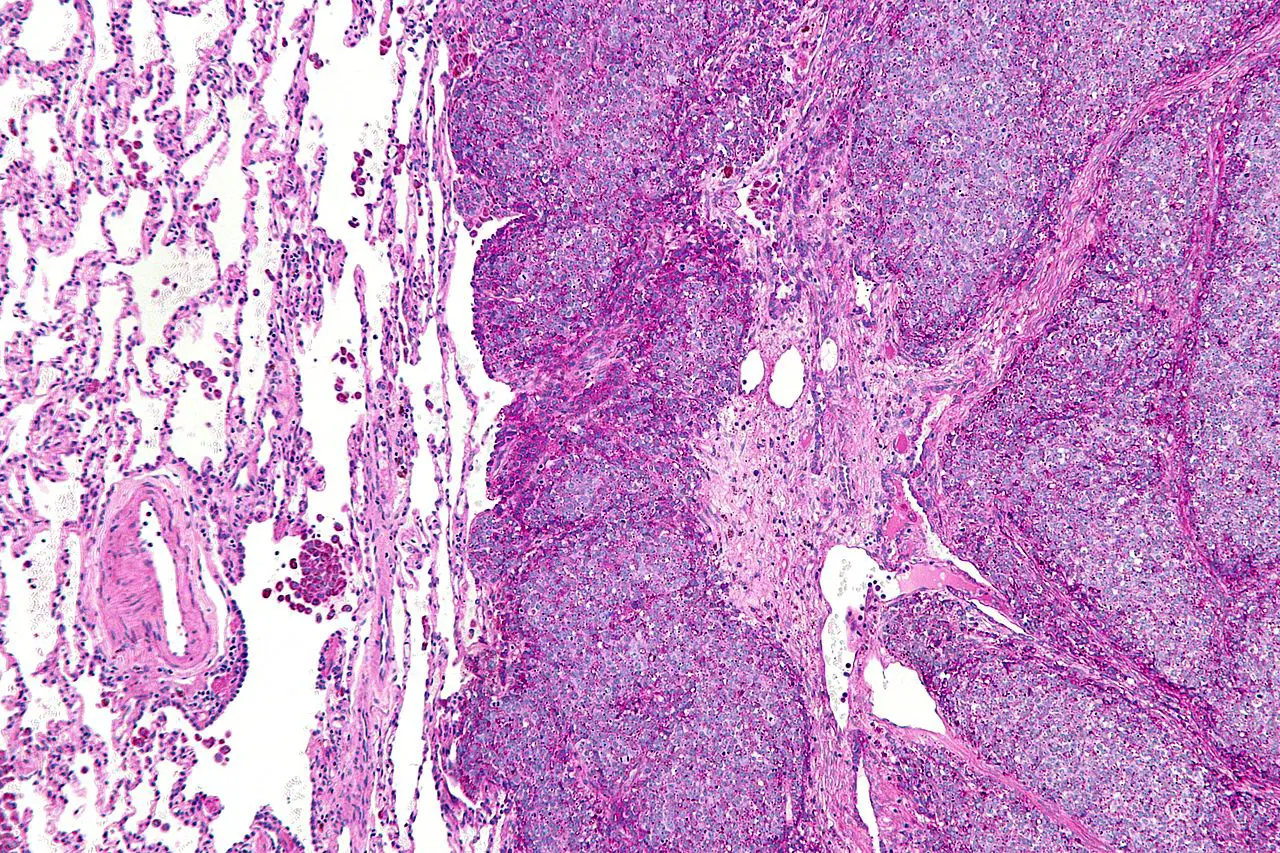

Саркома Юинга — это агрессивное злокачественное новообразование, преимущественно возникающее у детей и подростков. Оно отличается высокой склонностью к рецидивам. Основная проблема терапии — развитие лекарственной устойчивости. Ученые предложили инновационный метод: применение микрочастиц на основе биосовместимого природного белка лактоферрина, эффективно взаимодействующего с раковыми клетками. Ключевую роль сыграл Институт Биологии Гена РАН, поставляющий лактоферрин. Институт тесно сотрудничает с Сеченовским Университетом, создавая технологии для иммунной инженерии, 3D-биопечати и клеточной терапии.

Тесты на клеточных культурах подтвердили, что микрочастицы обеспечивают контролируемое высвобождение вещества включая зависимость от уровня pH на протяжении 24 часов. Также они усиливают его токсичное воздействие на клетки. Система показала высокую результативность как против стандартных клеток саркомы Юинга, так и против линий, устойчивых к ключевому химиотерапевтику — доксорубицину.

Подробное изучение механизмов показало: одновременное действие микроносителей и OX72 запускает в опухолевых клетках процесс ферроптоза. Это особая форма запрограммированной смерти клеток, сопряженная с дисбалансом обмена железа и ростом окислительного стресса. Этот процесс, в отличие от стандартного апоптоза, сохраняет работоспособность даже в случаях выраженной невосприимчивости к лекарствам.

Важным достоинством системы является её избирательное действие. Лактоферрин эффективно связывается с рецепторами, которые в избытке присутствуют на поверхности раковых клеток. Это способствует направленному накоплению терапевтического средства непосредственно в зоне патологии.